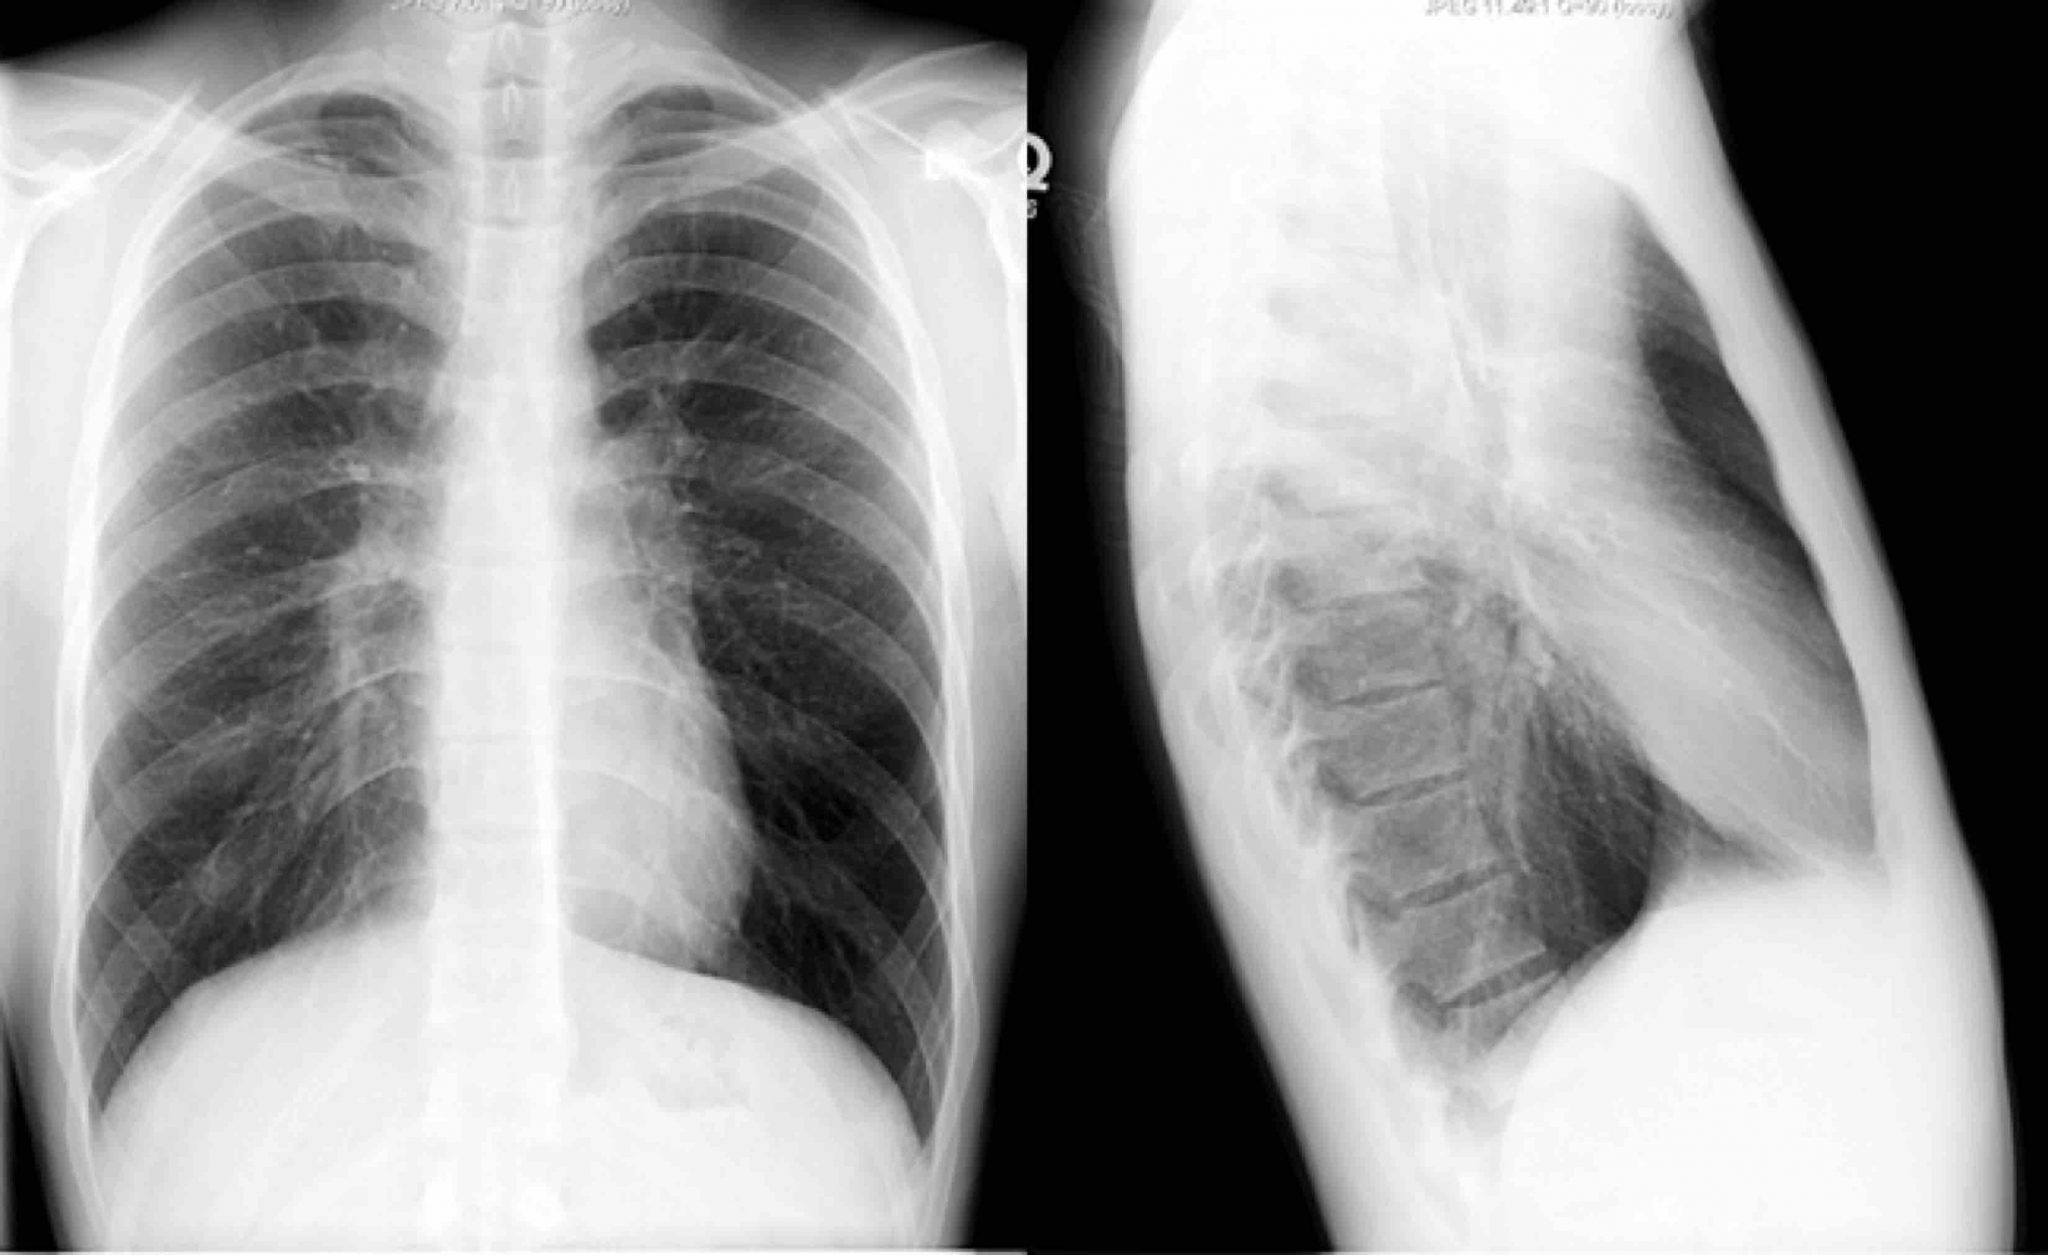

Basic Chest XRay Interpretation Tips and pointers to see it all!

Lightning Learning Basic Chest Xrays in Adults — EM3 Chest X Ray Interpretation Abcdefgh In fact every radiologst should be an expert in chest film reading. There are many approaches to cxr interpretation, each trying to ensure that key abnormalities are identified and no area is overlooked. Assessment of quality / airway. The quality of the image can be. A simplistic guide for doctors,. The popular abcdefghi approach for reading a chest x ray.. Chest X Ray Interpretation Abcdefgh.

Normal Chest XRay Labelled Anatomy PA View CXR Interpretation Ribs Chest X Ray Interpretation Abcdefgh In fact every radiologst should be an expert in chest film reading. The popular abcdefghi approach for reading a chest x ray. The quality of the image can be. A simplistic guide for doctors,. Including assessment of costophrenic angles. Assessment of quality / airway. Trachea, carina, bronchi and hilar structures. There are many approaches to cxr interpretation, each trying to. Chest X Ray Interpretation Abcdefgh.